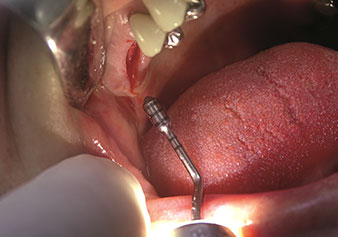

Hassas periotom (uç EX1)

Şekil 1: Hassas periotom (uç EX1).

Fotoğraf: © Dr Torsten Conrad (Bingen a. Rhein)

Sıklıkla hafife alınan uygulamalardan biri, alveolar yönetimin bir parçası olarak diş köklerinin veya kök parçalarının nazikçe çıkarılmasıdır. Şu anda iki modeli (W&H'ten EX1 ve EX2) mevcut olan hassas periotomlarla, özel olarak endodontik ön işleme tabi tutulmuş dişler veya ankilozik kökler de kolayca çıkarılabilir. Sonuç, sert ve yumuşak dokuları tamamen sağlam olan ekstraksiyon alveolleridir, çünkü genellikle onları açmak gerekli değildir.

Bu, daha sonra veya hemen implant bakımı için optimum bir temel oluşturur [şekil 1 ve 2, Dr. Torsten Conrad’ın (Bingen a. Rhein) onayı ile kullanılmıştır].